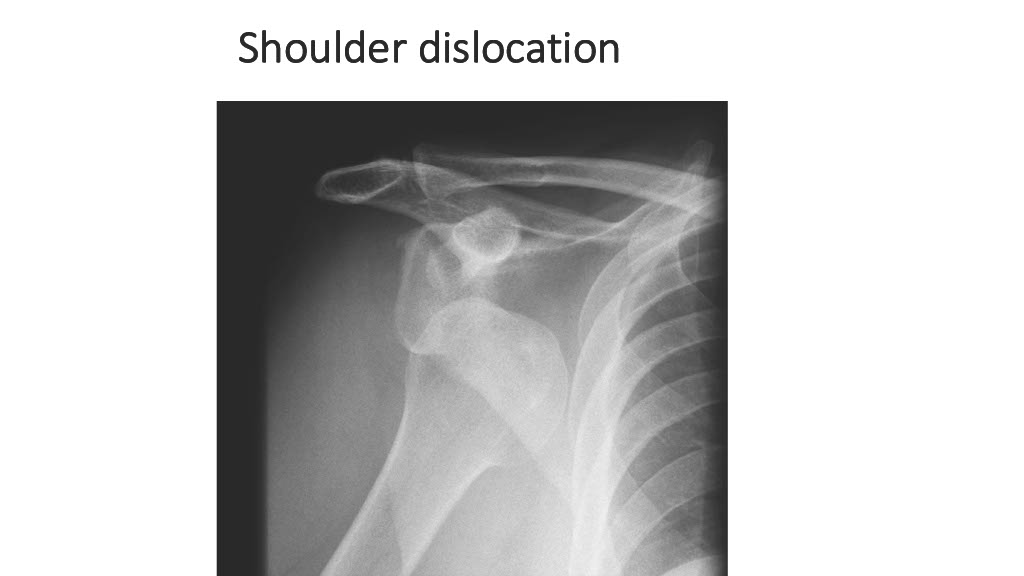

Vogrin, Matjaž, MD, PhD.

Department of Orthopaedics & Sports Medicine Institute, University Medical Centre Maribor, Slovenia

“Surgical treatment of knee injuries in skiing”

Prof. Matjaž Vogrin is an orthopaedic surgeon and specialist in arthroscopic surgery and sports injuries. He is chairman of the Institute of Sports Medicine ” at the Faculty of Medicine in Maribor, Slovenia, and head of the medical subdivision of the Slovenian National Olympic Committee.

He was chief physician of the Slovenian Olympic team at the 2012, 2016, 2021 and 2024 Olympic Games (London, Rio, Tokyo, Paris), official physician of the Slovenian national football team and head of the Slovenian medical team at the 2010 FIFA World Cup in South Africa. He has also been head of the medical team of FC Maribor ( UEFA Champions League and Europa League participants) since 1999. He has been an invited speaker at sports medicine congresses and conferences worldwide.

Surgical treatment of knee injuries in skiing